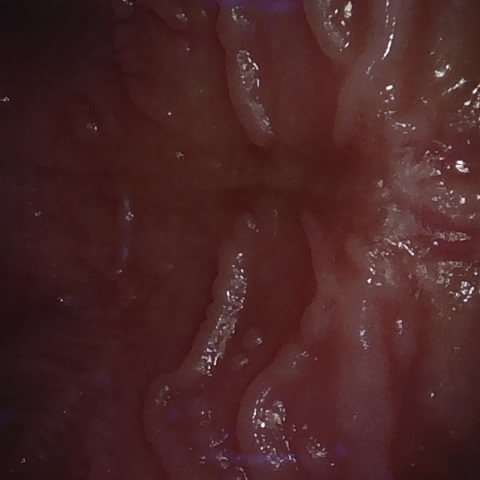

Image 704 / 1103

NHD39174

Annotated as "Good"

Original Image Rendering Image